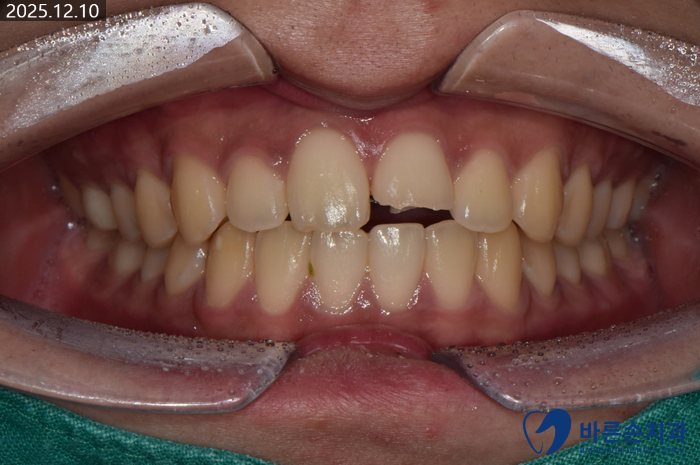

겨울철 넘어지셔서,

가운데 앞니 2개 중 하나가 반토막으로 부러졌네요..ㅠㅠ

이 환자분의 경우엔 통증도 있으시고, 신경관 가까이 까지 파절이되어

신경치료 후 크라운 치료를 계획했습니다!